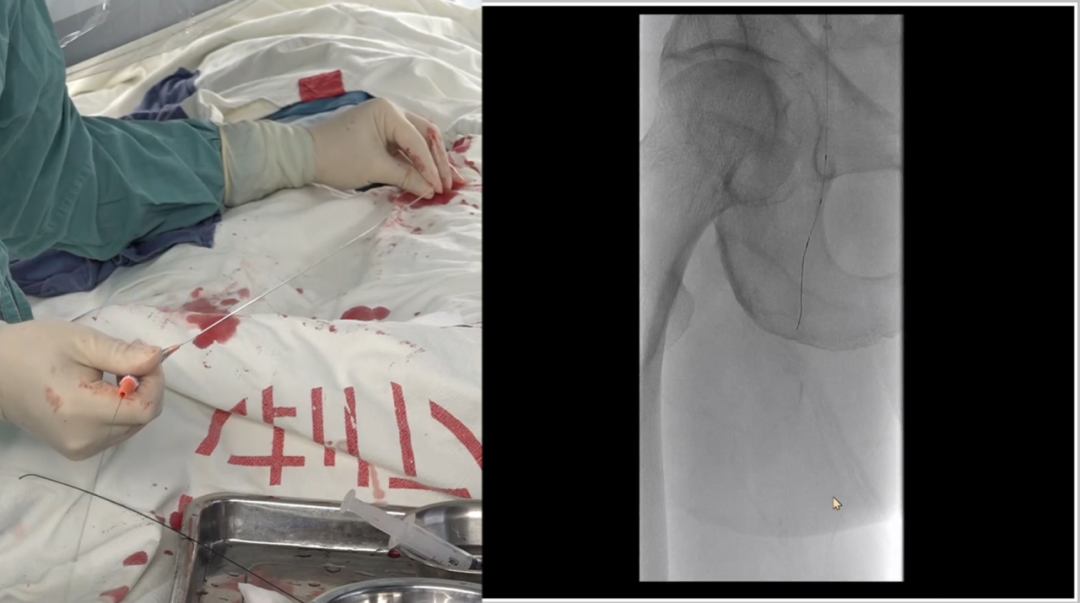

远端困境:

内膜下难以返回真腔,果断选择逆穿

导丝进入远端内膜下后,反复尝试返回真腔失败。为避免过度操作损伤远端流出道,团队决定行逆向穿刺(逆穿):

调整球管至左前斜20°~30°,在路图下定位穿刺点;

近端推注造影剂,透视下确认血管位置,穿刺成功(可见明显充盈缺损);

跟进V18导丝突破远端纤维帽,配合支撑导管完成对接。

逆穿的难点在于选择合适的对接位置,对接判断要点是导丝成袢后,通过近端Terumo导丝触碰,若有明显"碰触感",提示位于同一内膜下,可确认对接。